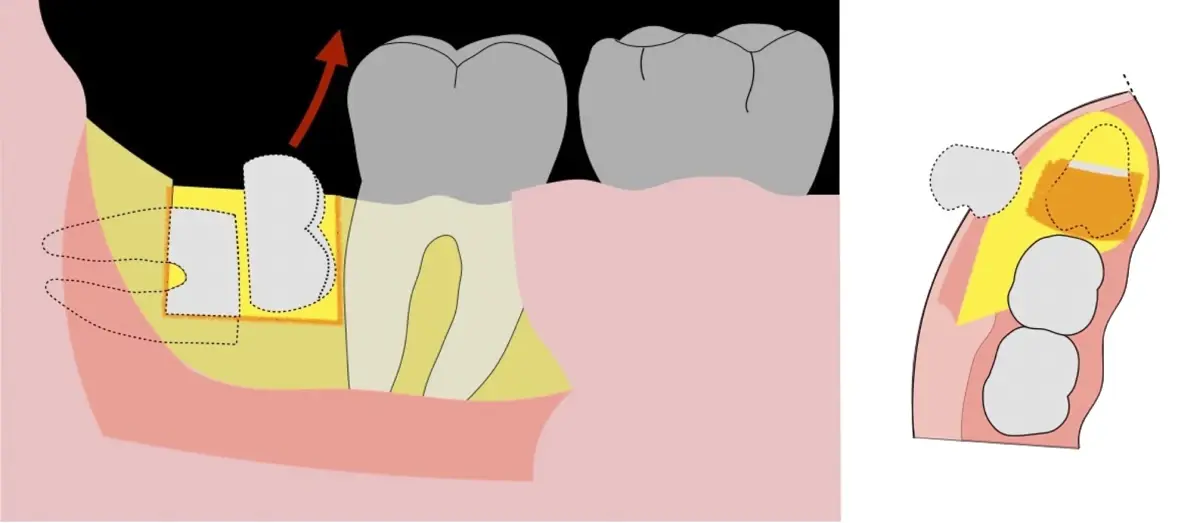

Es imprescindible conocer la ubicación de la tercera molar. Se puede emplear, adicionalmente a la evaluación clínica, herramientas radiográficas (panorámica y periapical) y tomográficas (Cone beam) para determinar la posición, grado de retención y proximidad a estructuras vecinas de riesgo como el nervio dentario inferior y así evitar lesiones (Figura 1).

El procedimiento se inicia colocando anestesia troncular para bloqueo del nervio dentario inferior y sus ramas. Luego, se establecerá el diseño de acceso según la disposición de la molar a extraer. Para fines didácticos, se explicará cómo se realizaría la extracción de la molar de la Figura 1: se realiza una incisión horizontal a nivel de la zona retromolar hasta llegar a distal de la segunda molar, continuándose con una incisión intrasurcular hasta mesial de la segunda molar, finalizando con una incisión vertical a espesor total hasta llegar a la línea mucogingival (Figura 2).